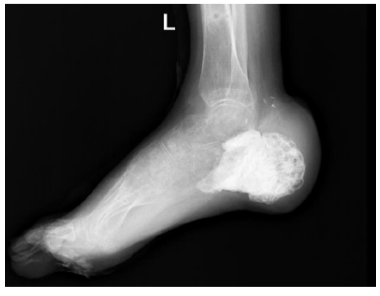

Хирургическое лечение застарелых переломов пяточной кости: обзор литературы

Последствия переломов пяточной кости вызывают стойкую инвалидизацию пациентов и снижение качества их жизни. Типичными проявлениями выступают деформация заднего отдела стопы, плоскостопие и подтаранный артроз. Стойкие посттравматические деформации с течением времени приводят к возникновению патологической биомеханики стопы и нарушению кинематики и кинетики нижних конечностей и таза.